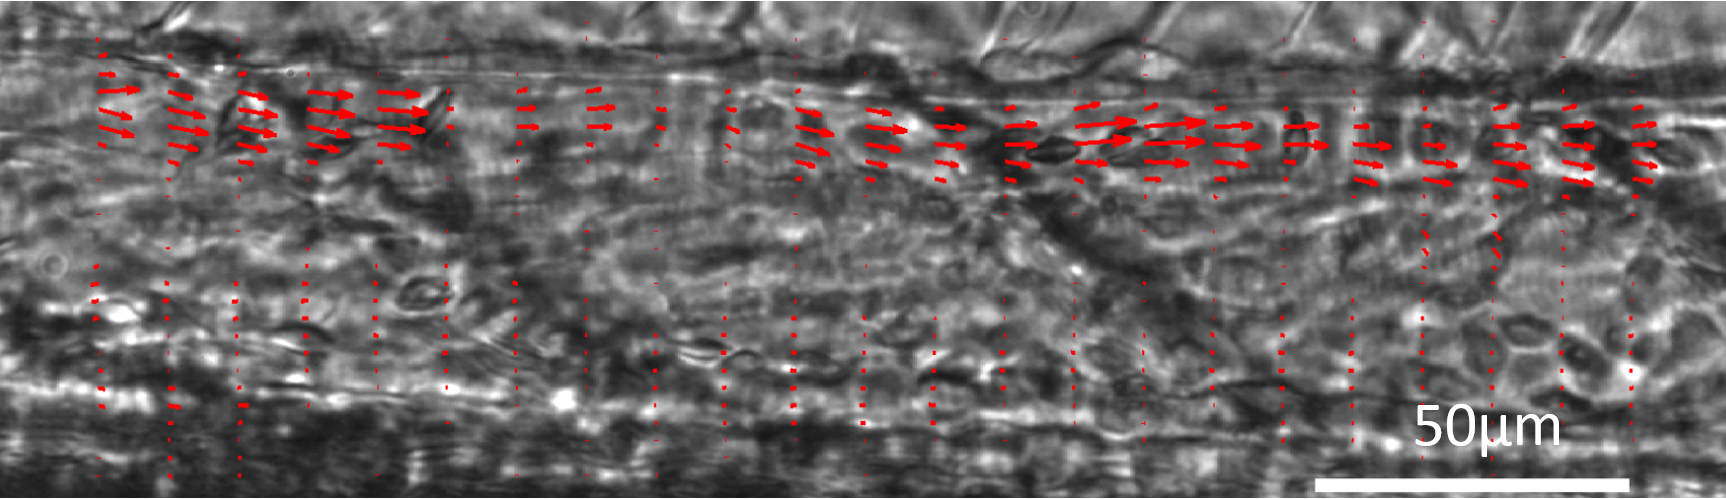

The in-vivo investigation of blood flow and shear stress is a standard parameter in biological research on vasculatory systems. We combine state-of-the-art videomicroscopy with high speed cameras. By using correlative image evaluation with background correction we are able to raise the signal-to-noise ratio to levels that do not require an additional labelling, facilitating sample preparation.